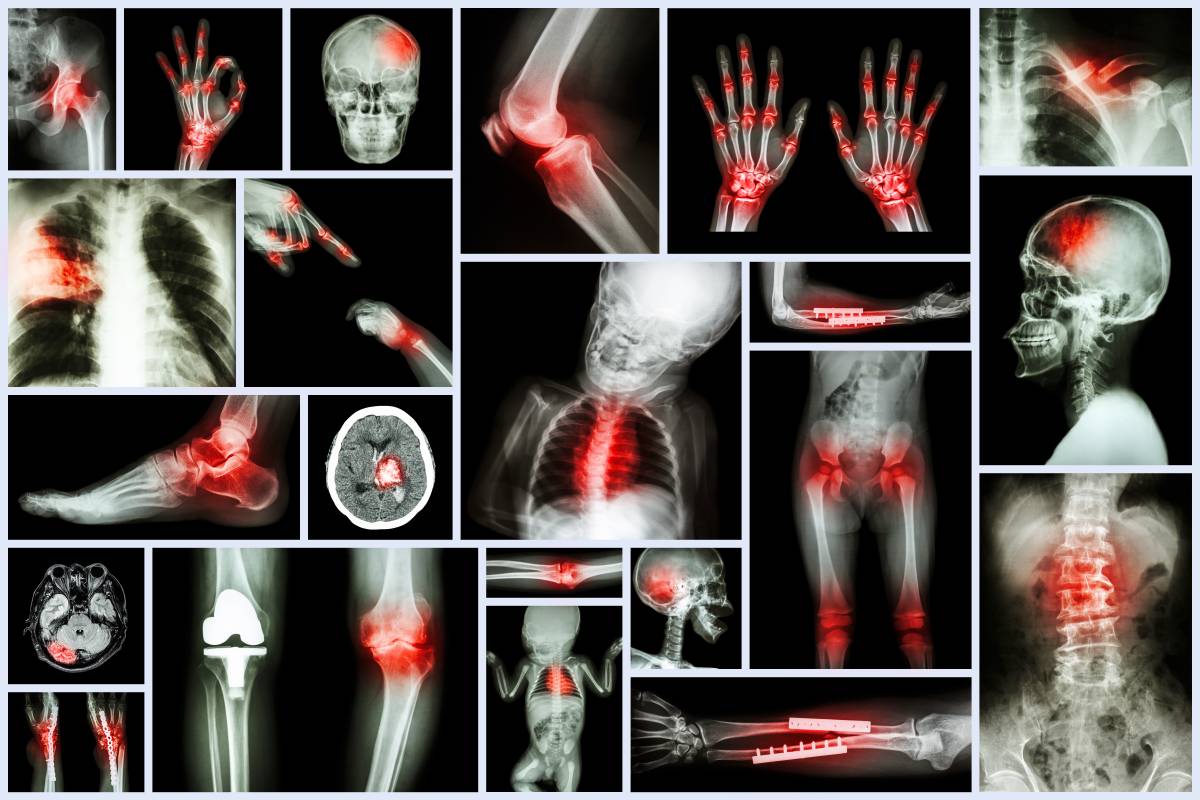

骨折以后及时进行治疗,大多数患者可以恢复原来的肢体功能。但“伤筋动骨一百天”,骨折的愈合需要一个过程,一般经过治疗后,需要长时间卧床,这就增加了膝关节粘连、僵硬及关节周围肌肉萎缩等并发症的发生几率,给膝关节功能恢复增加了一定的难度。那么,骨折大约需要多久可以康复?进行哪些训练可以加速康复进程呢?一起来了解一下吧。

骨折部位的愈合过程大致可以分为4个阶段。

1.肉芽修复期:发生骨折时,除了骨组织被破坏,周围的软组织也同样会受到不同程度的影响,引起血管破裂、出血,形成血肿。伤后4~5小时,骨折部位血液开始凝固,形成含有网状纤维素的血凝块。另外,毛细血管、成纤维细胞等从骨折两端同时向血肿内生长,这些新生毛细血管、成纤维细胞和吞噬细胞从各个方向侵入血凝块和坏死组织,通过不停地分裂达到清除积血、形成肉芽组织的目的。肉芽组织进一步转化,成为纤维组织,将两个骨折端连接在一起形成纤维愈合,称作“血肿机化”。这一过程大约在2~3周内完成。

2.原始骨痂形成期:骨折端附近的外骨膜增生,新生血管长入其深层,开始膜内骨化,髓腔内的内质膜同时产生新骨,但较缓慢。由血肿机化而形成的纤维组织大部分转变为软骨,经增生变形而成骨。这个过程约在伤后6~10周内完成。

3.成熟骨板期:患处的新生骨小梁逐渐增加,排列也逐渐规则。此期也叫“临床愈合期”,在伤后8~12周内完成。

4.塑形期:再生的骨需要根据人体力学进行不断的改建,即不断有破骨细胞吸收和成骨细胞形成新骨。如果骨折对位对线良好,骨折处可完全恢复原状,髓腔重新畅通,不留任何骨折痕迹,最终达到正常骨骼的结构。